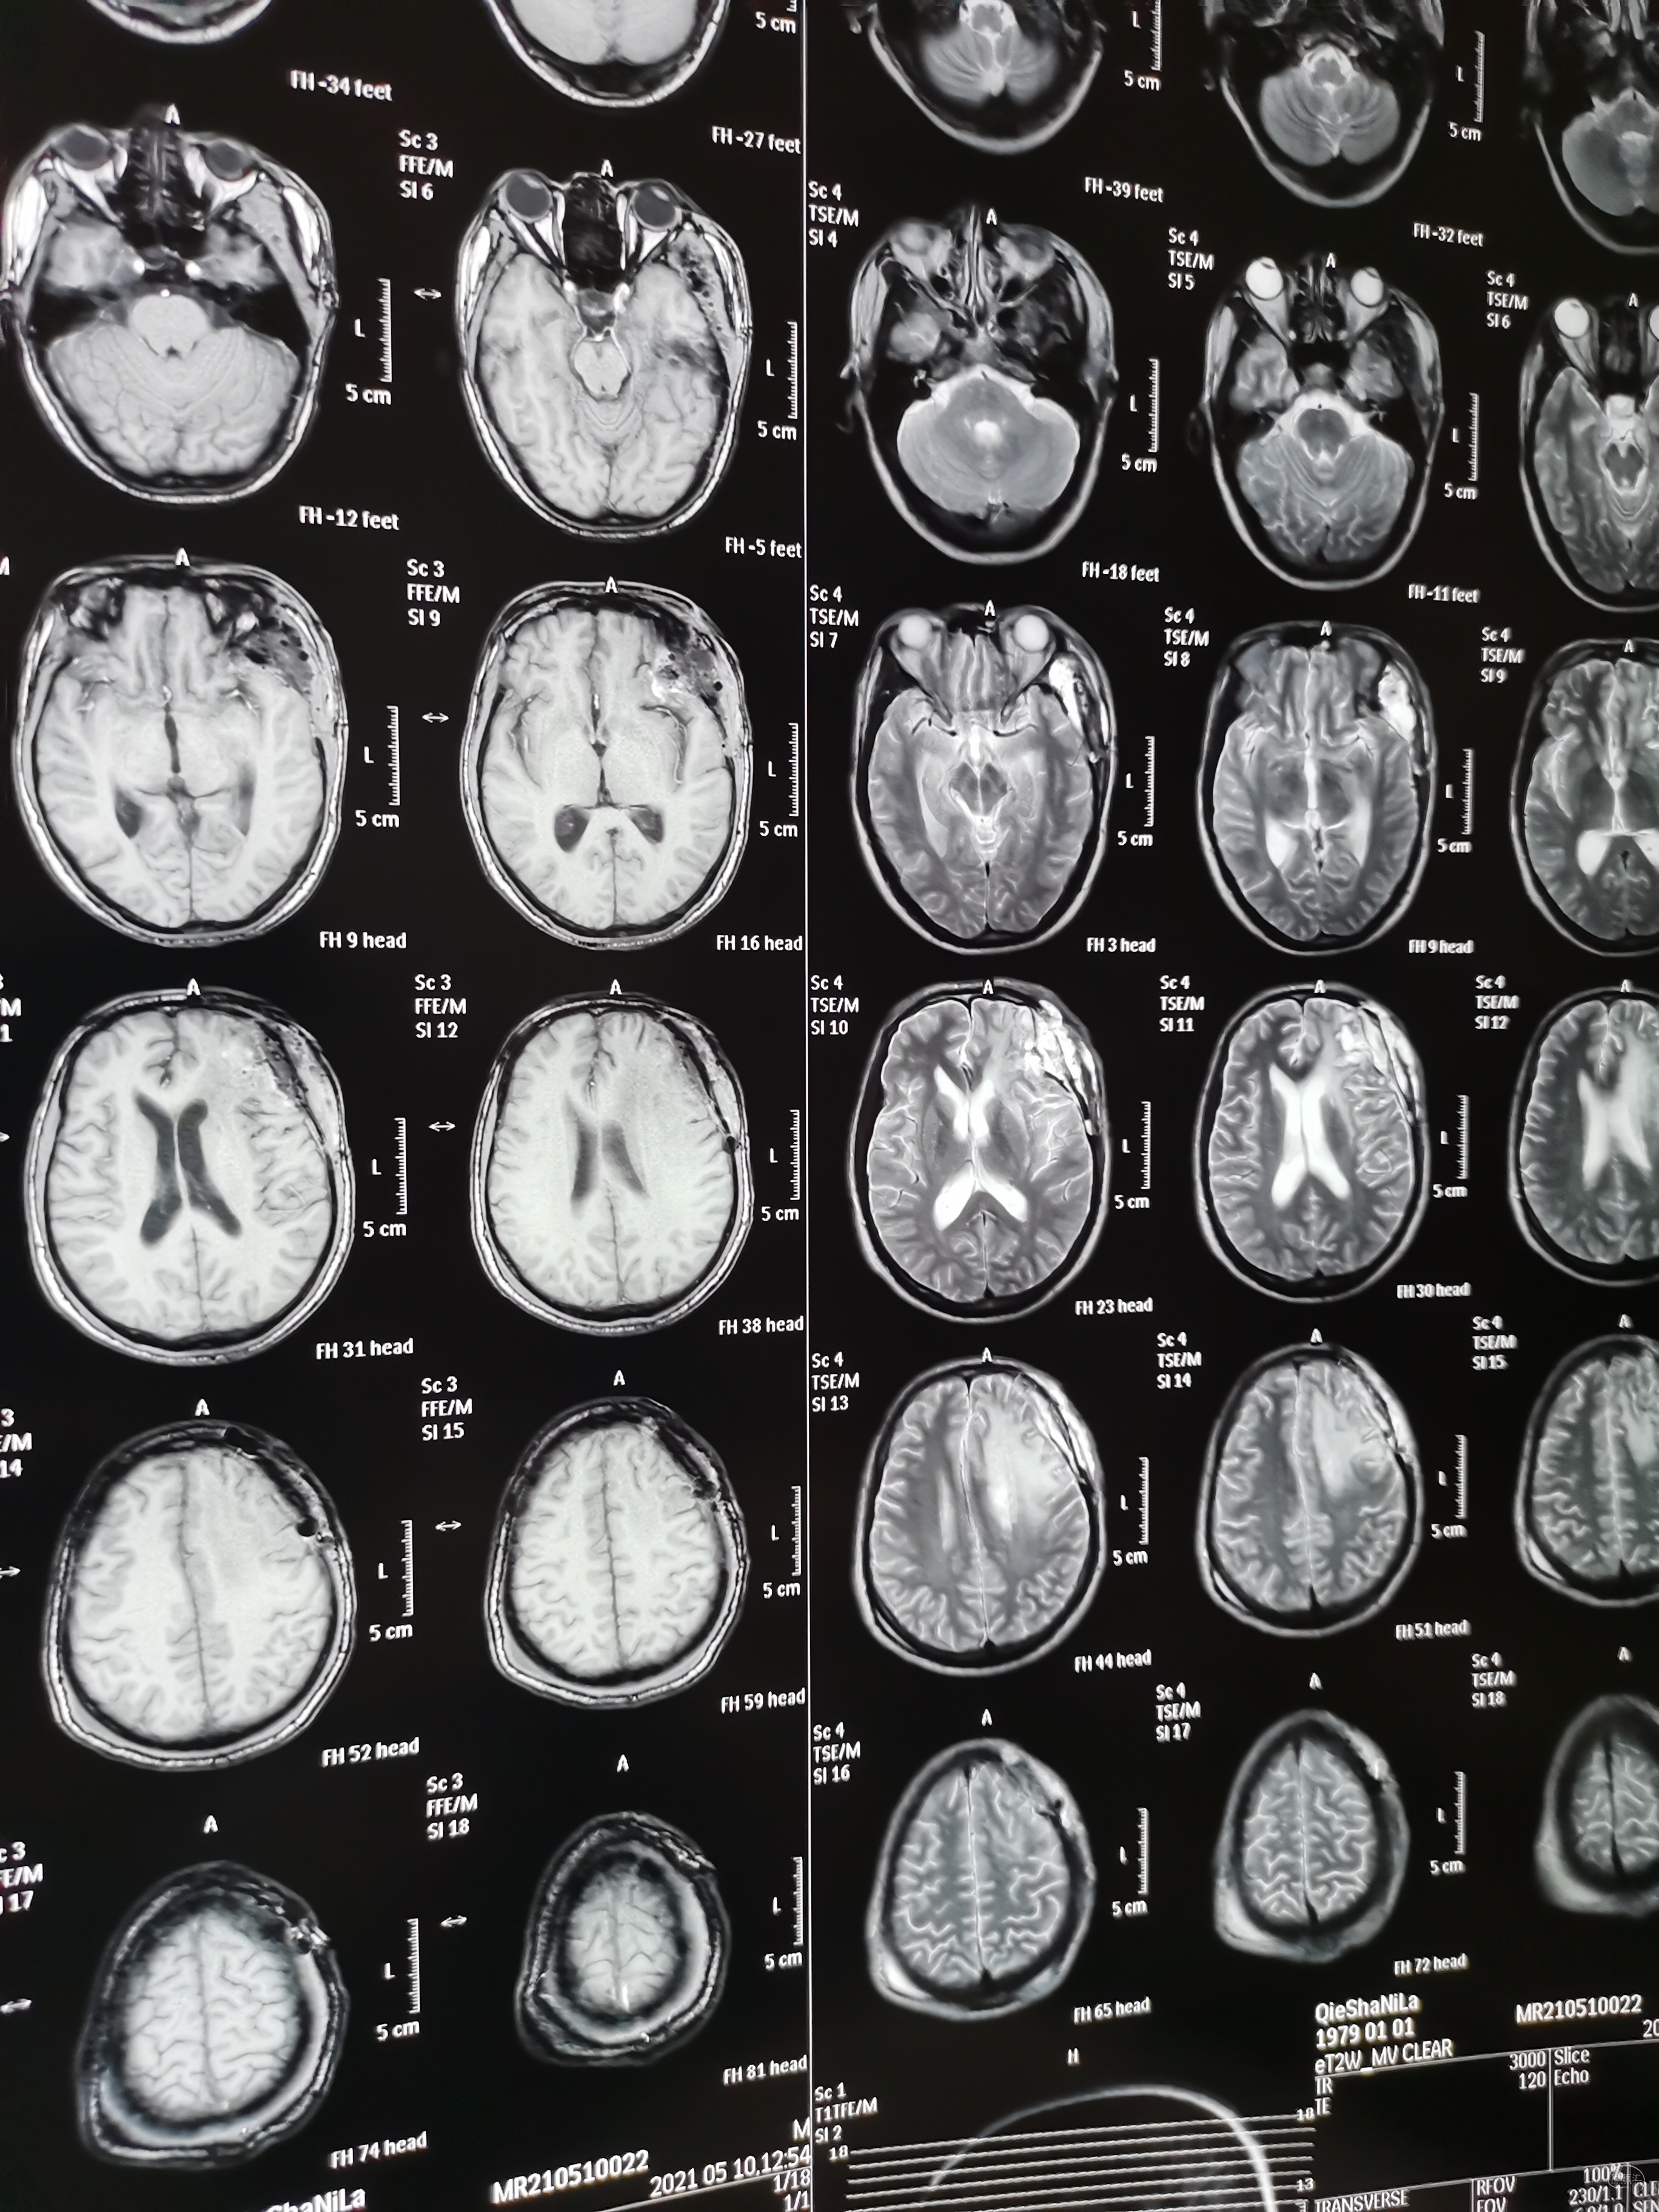

术前头颅MRI检查提示为左侧额叶占位性病变,增强强化均匀,似有脑膜征。考虑为脑膜瘤,蝶骨棘外侧型。

术后头颅MRI检查切除满意